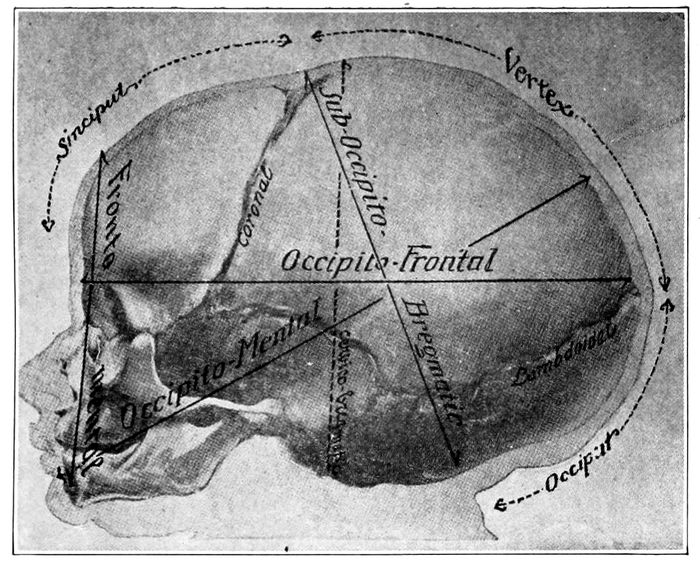

Fig. 22 A.—Child’s head at term (from side), showing diameter. (American Text Book.)

Fig. 22 B.—The child’s head at term (from above), showing diameters and fontanelles. (American Text Book.)

The important diameters of the head, with their measurements

and names, are as follows:

Nape of neck to center of bregma, 9.5 cm.—Suboccipito-bregmatic

diameter. Occipital protuberance to root

of nose, 11.25 cm.—Occipito-frontal diameter. Between

the eminences of parietal bones, 9.25 cm.—Biparietal

diameter. Between anterior ends of coronal sutures, 8

cm.—Bitemporal diameter.

The smallest circumference is that of the suboccipito-bregmatic

plane, which comes into relation with

the brim of the pelvis when the flexion of the head is

complete. It measures 27.5 centimeters.